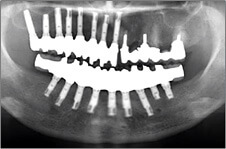

1983年に東京歯科大学が日本で最初にオッセオインテグレーテッドインプラントの概念とその治療法を紹介して以来、口腔インプラント療法は急速な進歩を遂げ、現在では、咀嚼障害や審美障害の改善手段として、長期間にわたる良好な治療成績が確認されています。千葉歯科医療センター口腔インプラント科では、近年、ますます複雑、多様化する患者様のニーズに応えるため、最新の設備や充実したスタッフを配備し、安心・快適・便利を実感できる診療科をめざしています。また、インプラント埋入手術時の鎮静法の併用、基礎疾患を持っている患者様の全身管理下での処置、骨移植、口腔内軟組織移植等の関連手術を行う設備体制を整え、大学医療機関の特色と利点を最大限に生かした治療を心がけています。

歯の欠損が多い場合(無歯顎者など)

部分入れ歯や総入れ歯などを使う必要がある歯の欠損に対するインプラント治療では、入れ歯と比較して違和感が少なく、咀嚼や発音などの機能回復が期待できます。また、欠如部以外の残存歯の治療が必要になる場合も、初診時からメンテナンスに至るまで一貫した包括的治療を行っています。また、インプラント埋入部位の骨が不足していたり、その他の要因でインプラント療法を断念されていた患者様に対しても、各分野の専門スタッフが高度な診断技術により対応をしています。